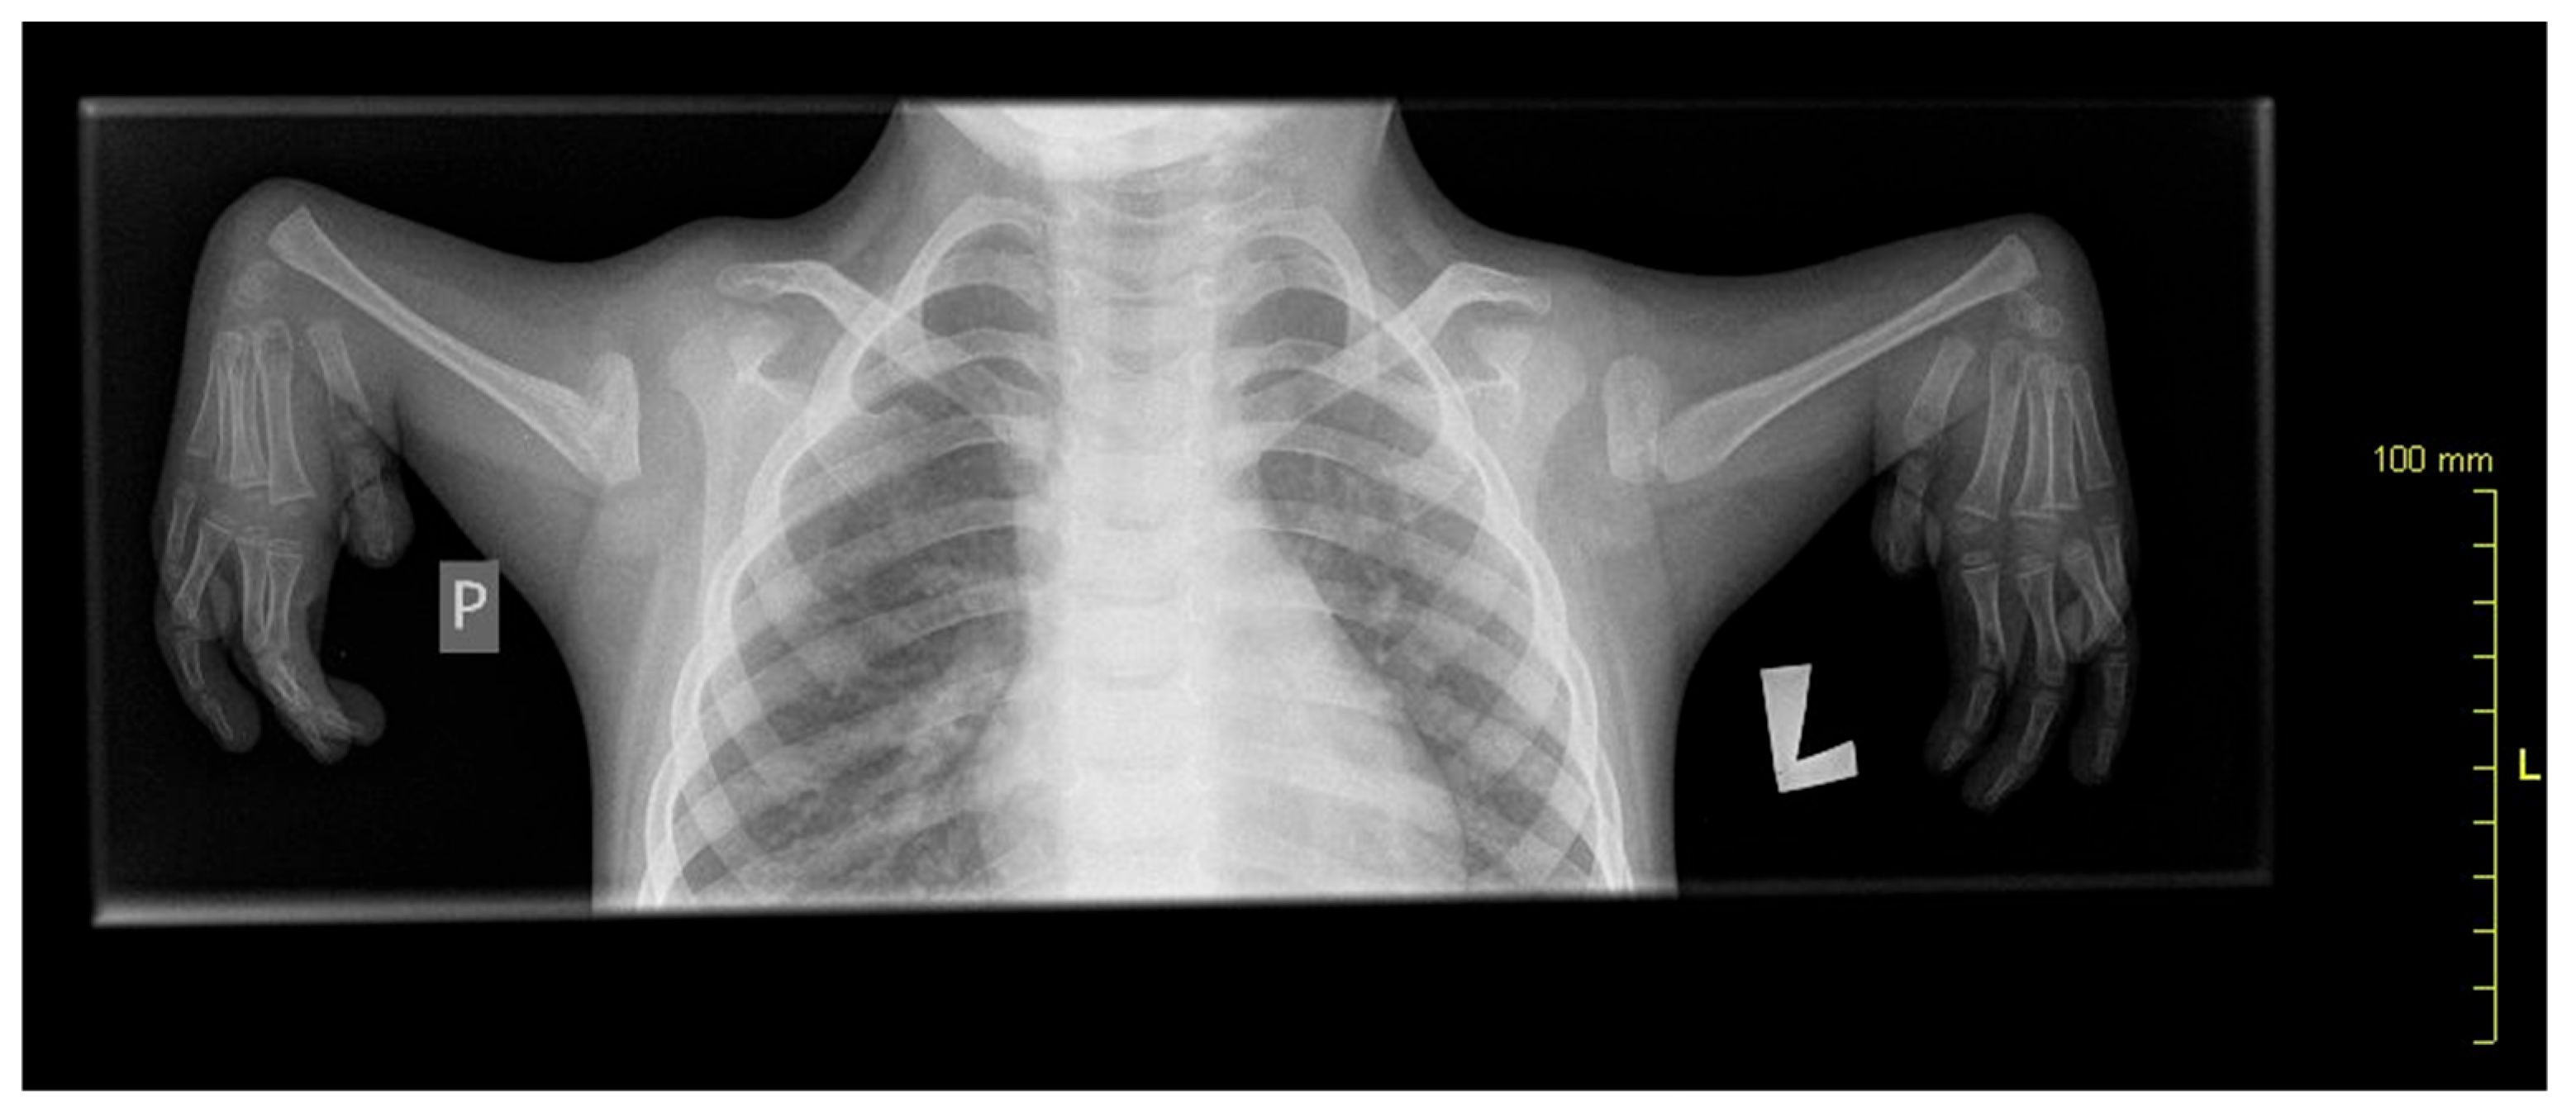

A 10-year-old patient with congenital upper limb deformity was evaluated (Figure 1). In the posture analysis, the following observations were made:

Figure 1. X-ray showing radial aplasia. Note that the bones of the hand appear normal.